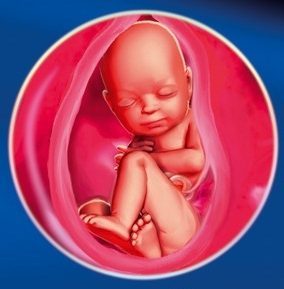

Ворушіння на 34 тижні вагітності стали зовсім незначні, тому як плід вже досить великий і йому просто не вистачає місця, щоб робити активні рухи.

Тепер у малюка стало ще більше білого енергоємного жиру, який становить 8% від загальної маси дитини. Завдяки йому, у малюка стала рівна шкіра без зморшок і вона не яскраво червоного кольору, а рожева, як і у всіх немовлят. Волоссячко на його голові стають все густіше, і майже зник зародковий пушок. Малюк, як і мама, вже починає готуватися до появи на світло, тому у нього стало формуватися ще більше первородного мастила. Зараз плід дуже зайнятий зміцненням своїх кісткових тканин, тому йому доводиться набирати кальцій з маминого організму.

Якщо дитина з'явиться на світ саме в цей період, то його вважатимуть достроково народилися. Справа вся в тому, що загальна зрілість дитинку і розвиток легеневих тканин вже дозволяє дитині жити без будь-яких додаткових апаратів. Вони самі дихають і ніяка інтенсивна терапія їм не знадобиться. Кожен лікар зможе подивитися готовність легких до першого подиху за допомогою пункції плодового міхура. Таким чином, перевіряється рівень сурфактанту.

Розмір і вага плоду на 34 тижні вагітності становить 32 см і 2250 кг відповідно. Але варто зазначити, що ці показники можуть змінюватися в залежності від фізіології матусі і розвитку дитини.